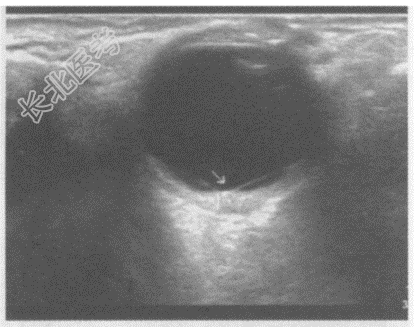

- 单项选择题临床资料:男, 57岁,自诉近视30余年, 近1月右眼视物模糊,眼前阴影遮挡, 视力下降,当地医院诊断糖尿病视网膜痛变。眼科检查: 视力:右0.05、左0.6。眼底右眼窥视较模糊, 视盘边界不清,水肿, 血管走行尚可,视网膜大量散在点片状出血, 火焰状。

超声综合描述:右眼玻璃体暗区内可见带状回声, 其尖端与视盘相连,两边分别与周边球壁相连(箭头所示), 呈“V“形,运动试验、后运动阳性, CDFI:带状回声内可见动脉血流信号, 且与视网膜中央动脉血流信号相延续。